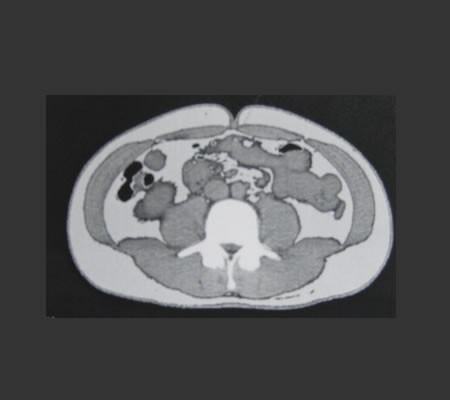

もうね、恥も外聞もないから、いっその事CT画像を大公開☆

どう?すごい腹周りでしょ?!

白い部分が全部脂肪だぉ♪

でもね、、、ひとつ気になる点があって、2007年との比較画像があったんだけれど、、、

あんまり変わって無い気が・・・

要するに昔から腹周りデブっちょだったという衝撃事実(涙)

数値的には一切肥満値は出ていないのよ!!!

だからいたって健康という訳♪